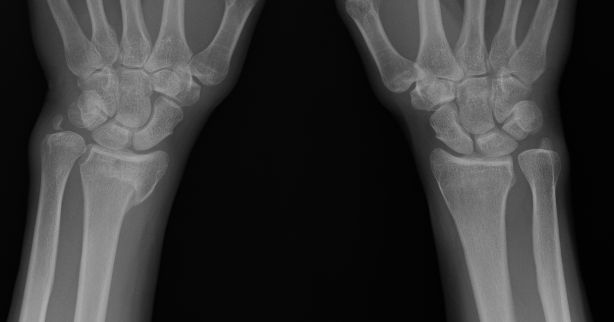

Xray

Bilateral xrays

PA film in neutral

- wrist neutral

- elbow & shoulder at 90°